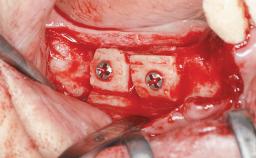

A 47-year-old woman who had suffered from aggressive periodontitis requiring a number of periodontal interventions over more than 10 years was referred by her general dental practitioner and periodontologist for bone augmentation and implant therapy. Her failing dentition had already been scheduled for extraction. The patient expressed a desire for implant-supported fixed restorations and esthetic improvement of her lower face. She had agreed to consult with a maxillofacial surgeon after the referring dentist had suggested bone augmentation. An initial examination by the maxillofacial surgeon revealed mobility of all residual teeth in a patient who was very unhappy with the function of her removable partial dentures. Due to periodontally migrated flaring teeth and loss of occlusal support, the vertical dimension of occlusion was dramatically reduced. The patient was displeased with her lower face because of deepened nasolabial, commissural, and supramental folds.